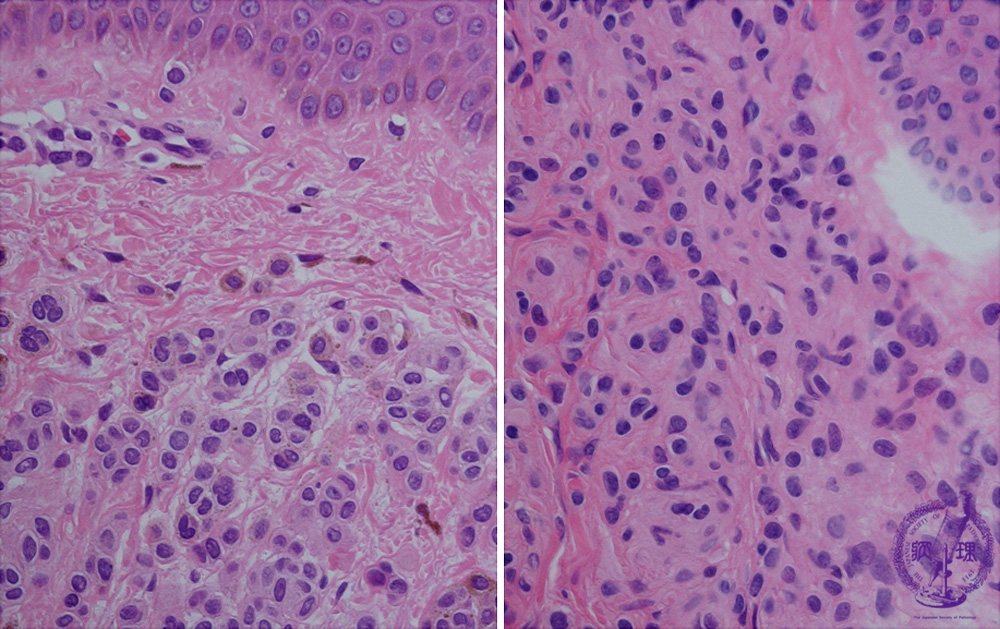

- (5)Melanocytic nevus (intradermal, junctional, compound)

Nevus cells form nests at the superficial dermis. Sometimes multinuclear nevus cells also exist (left). At the deep dermis, smaller nevus cells scatter. Cytoplasmic border of the nevus cells are obscure.